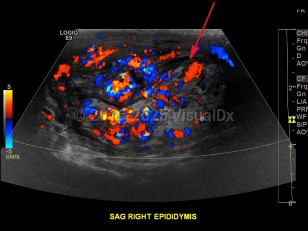

Symptoms of epididymo-orchitis usually develop over 1-2 days, although some patients will complain of a more gradual onset of symptoms. The primary complaint is swelling of the scrotum associated with pain. Urethral discharge is common. Fever may or may not be present. On palpation, swelling in the posterior scrotum localized over the involved epididymis can be appreciated. There may be a hydrocele. There may be erythema overlying the area of swelling. Pain should improve within 72 hours after treatment, although inflammation may persist for a few weeks.